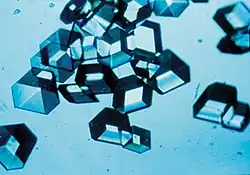

Les premières insulines étaient purifiées à partir de pancréas de bœuf et de pancréas de porc. Dans les années 1930, diverses préparations ont permis d'obtenir des formes d'action prolongée de l'insuline par cristallisation en présence de zinc, ou prolongation de temps de résorption sous la peau par l'adjonction de protamine (insuline NPH, préparée par Hagedorn).

L'allongement du délai d'action se fait essentiellement par adjonction de zinc ou de protamine dans la solution d'insuline, permettant la formation de cristaux ou de précipités dont la diffusion vers le sang est beaucoup plus lente.